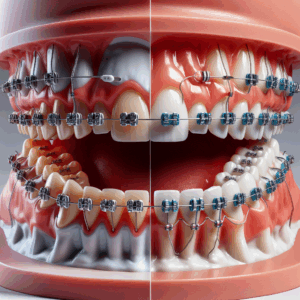

Metamorfoza uśmiechu stała się popularnym tematem w dziedzinie stomatologii estetycznej, a wiele osób zastanawia się, czy wszystkie zabiegi należy przeprowadzać jednocześnie, czy można je rozłożyć na kilka wizyt. Dzięki nowoczesnym metodom, takimi jak stomatologia estetyczna Kraków, pacjenci mają możliwość dostosowania procesu do swoich potrzeb.

Metamorfozę uśmiechu można przeprowadzać etapami, co pozwala na stopniowe wprowadzanie zmian. Proces rozpoczyna się zazwyczaj od konsultacji estetycznej oraz cyfrowej analizy uśmiechu (Digital Smile Design). Koszt tej konsultacji wynosi około 2000 PLN. Po jej ukończeniu pacjent otrzymuje spersonalizowany plan leczenia, uwzględniający ich oczekiwania oraz potrzeby.

W zależności od celów pacjenta, możliwe jest zastosowanie różnych zabiegów, które można wykonywać w dogodnym tempie. Można zacząć od:

- Wybielania laserowego – zabieg, który skutecznie rozjaśnia szkliwo nawet o kilka tonów podczas jednej wizyty.

- Bondingu – metoda bezbólowego zamknięcia szpar w zębach, która może być zrealizowana w jednej wizycie i nie wymaga znieczulenia.

- Licówek porcelanowych – trwałe rozwiązanie pozwalające na istotną zmianę koloru i kształtu zębów.